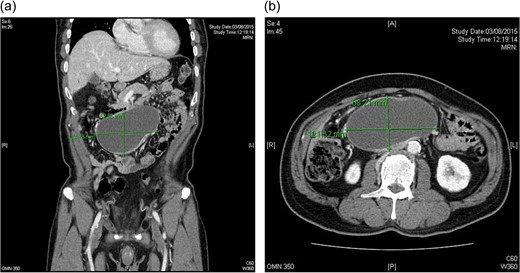

CT scan: 12.4 × 7.1 × 8.9 cm oval cystic lesion over central lower abdomen abutting loop of small bowel with compression on IVC, could represent a mesenteric cyst. No adrenal lesion (a and b).